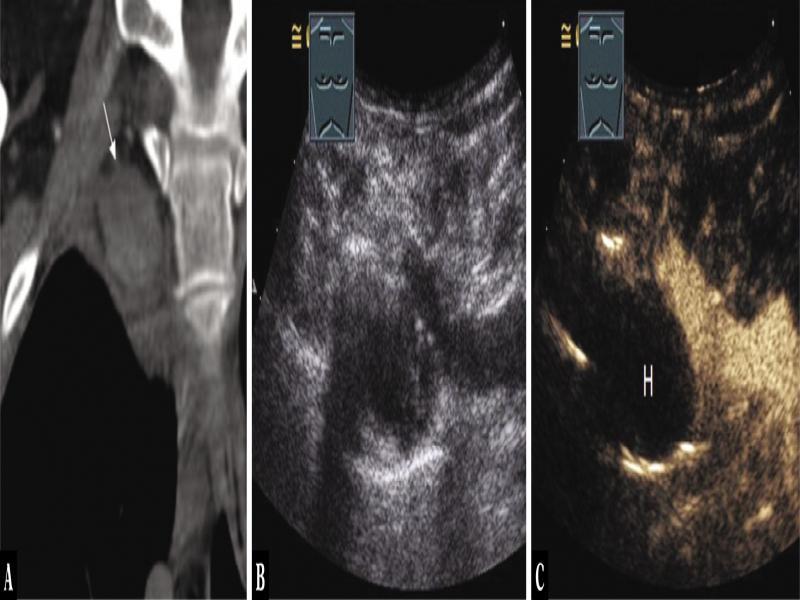

Fig. 4.

A 43-year-old female patient admitted for ultrasound-guided biopsy due to mediastinal tumor (arrow) in the anterior mediastinum as an incidental finding on computed tomography after an intensive care stay (A). Thoracic ultrasound indicated a complex hypoechoic tumor (B), which showed no enhancement on contrast-enhanced ultrasound, as in hematoma (H) (C). A biopsy was not performed due to anamnestic central venous catheter. The tumor showed spontaneous regression